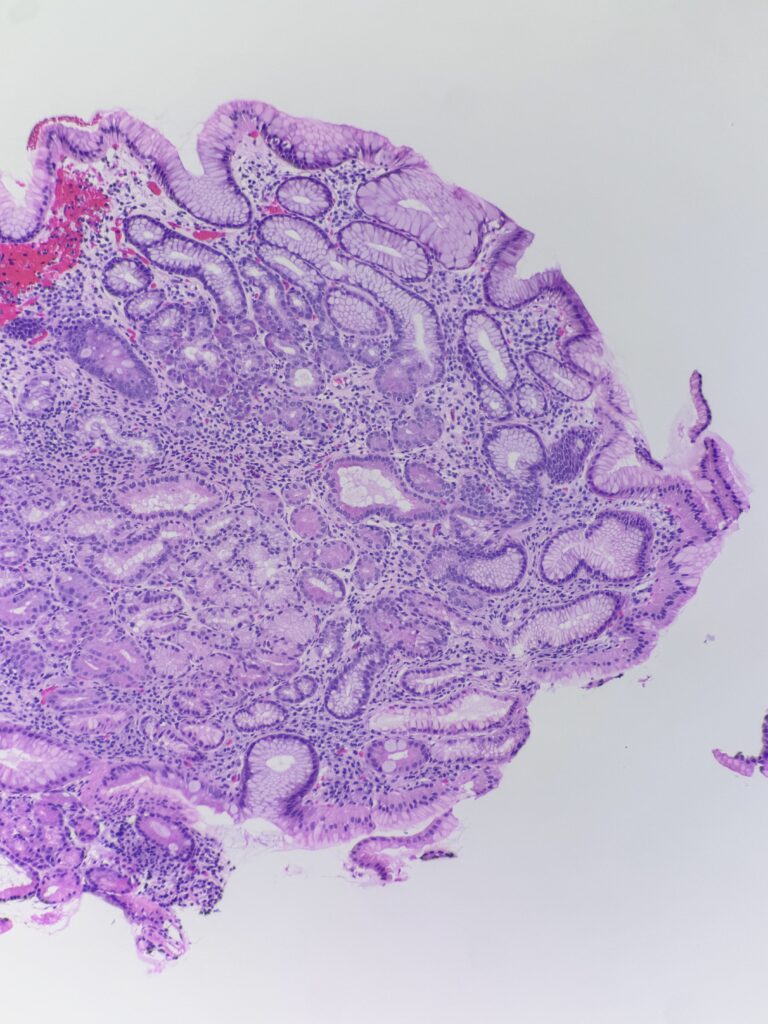

Histology:

Diagnosis: Autoimmune metaplastic atrophic gastritis

Diagnostic notes: As compared to H. pylori gastritis, the inflammation is predominantly in base of the mucosa extending to the superficial mucosa. There is loss of oxyntic glands, intestinal metaplasia, pancreatic acinar metaplasia and nodular and linear enterochromaffin like (ECL) cell hyperplasia. Gastrin stain can be used to differentiate antral vs. body mucosa – gastrin stain is positive in the antrum.